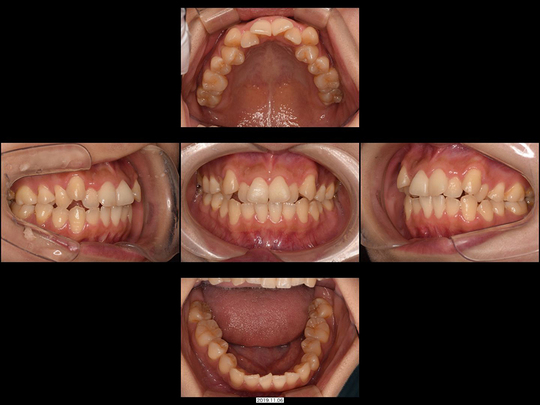

Kさん 40代 女性

矯正前

画像をクリックで拡大

矯正後

左上の前歯1本が反対咬合になっているのが気になっておられました。改善するには、そこの歯を抜いてブリッジにするしかないという診断を受けたことがあるそうです。しかしカウンセリング時に細かくお話を伺ったところ「抜いたり削ったりしたくない、今よりも磨きやすくなりたい。右の古い前歯の色が変わっているのも気になる」とのことでした。

右上の前歯は歯ぐきの色が黒くなっていました(メタルタトゥー)ので、矯正治療前に古い金属の土台を撤去。「プロビジョナルレストレーション」とよばれる自費診療の仮歯を使用して、左側の反対咬合の歯を動かす際のスペースを確保。歯の移動中に、メタルタトゥーによる黒ずんだ歯ぐきをレーザーにて対応しました。ご了承のもと、右上前歯はセラミック治療を行っています。非抜歯、上だけの部分矯正です。

治療の期間・回数

12か月、15回

​費用

614,000円